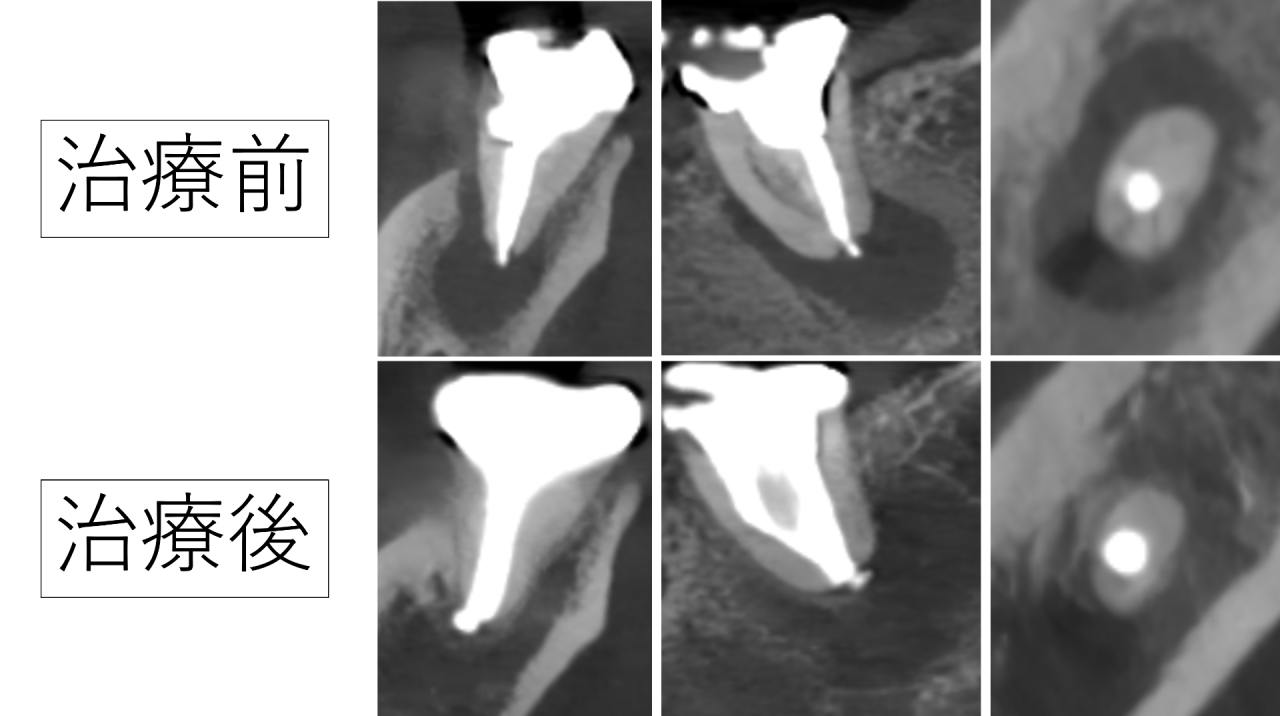

1年後、大きな根尖病巣は消え骨の再生が確認できました

そして1年後にCTで確認したところ、治療前に大きく黒く写っていた根の先の病巣は改善し、骨の再生が確認できました。

しかし、精密な根管治療を行うことで、1年後には病巣の改善と骨の再生が確認できました。